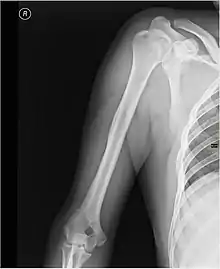

Каркасом плеча служит плечевая кость.

При травмах плеча возможно повреждение нервов и сосудов, а также переломы плечевой кости, наиболее частой локализацией которых является шейка плечевой кости.[1]